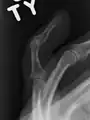

Un doigt en maillet résulte généralement d'une hyperflexion de la phalange distale[1]. Cela se produit généralement lorsqu'un ballon percute un doigt tendu et le bloque. Il en résulte soit une lésion du tendon soit un arrachement osseux par le tendon qui reste intacte. Le diagnostic est généralement basé sur les symptômes et confirmé par des radiographies.

Le diagnostic est généralement basé sur les symptômes et confirmé par des radiographies[1]. La lésion peut être accompagnée d'un œdème et d'une ecchymose[3].